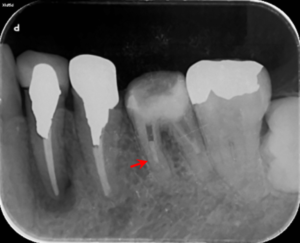

左下6番の歯の根の中の折れている器具を除去した後のレントゲン写真です。矢印赤のところにあった器具が除去されていることがわかります。